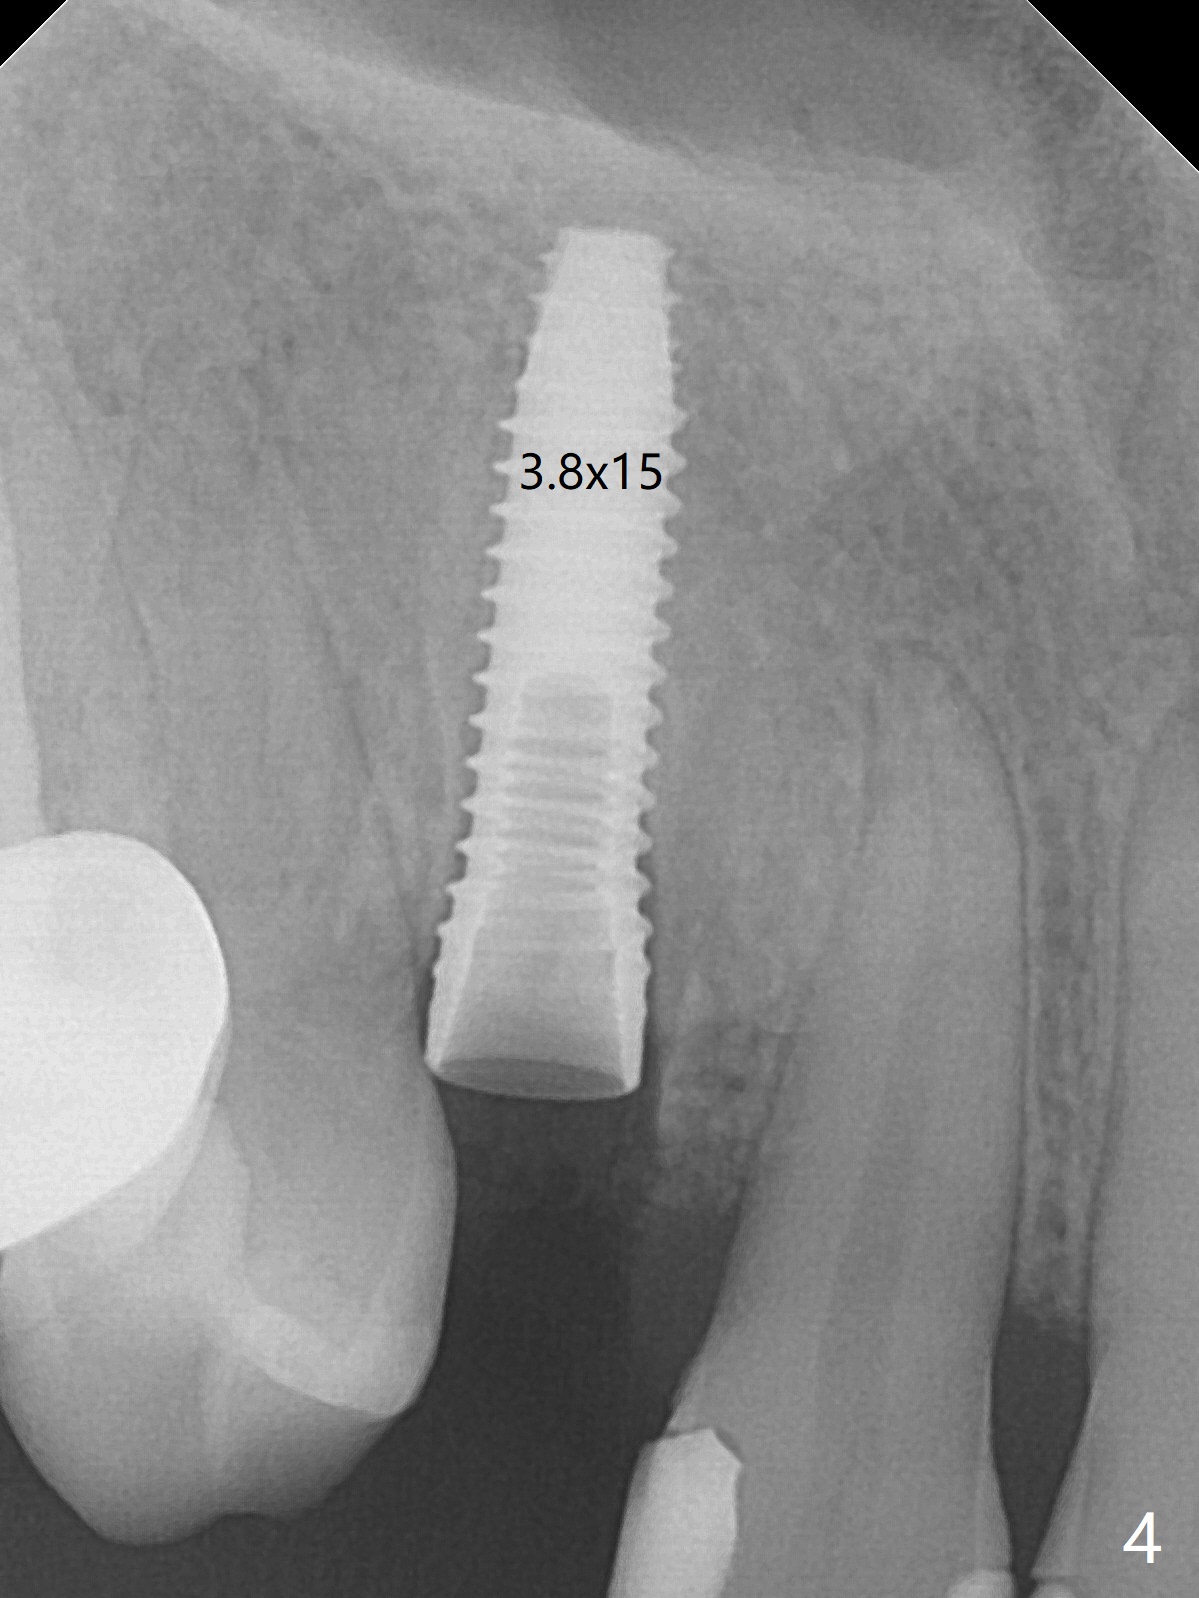

When the tooth #6 with loose crown and post (Fig.1) is extracted, there is no granulation tissue in the socket with the thin intact buccal plate. As planned, osteotomy is initiated in the mesio-palatal slope of the socket (Fig.2 red dashed line). After osteotomy for 3x20 mm (gingival level), a 3.8x15 mm dummy implant is placed partially (Fig.3 D). A final implant with the same dimension is placed with > 50 Ncm (Fig.4). Before and after placement of a 4.5x5(3) mm abutment, Vera graft is placed in the remaining socket space (mainly buccal, Fig.5 *). As routine, an immediate provisional is fabricated with occlusal clearance. The gingiva looks healthy around the provisional 1 week postop (Fig.6 P). Adjust and polish the mesioocclusal composite at #5 if necessary before impression. The bone graft appears to remain in place 4.5 months postop (Fig.7). A bevel buccal subgingival margin is placed prior to impression. The bone density around the coronal portion of the implant increases 9 months postop (4 months post cementation, Fig.8). There is no gingival erythema or edema around the implant crown at #6 ten months post cementation (Fig.6, as compared to preop condition and that of the neighboring crown (*)). Both the buccal and palatal plates are thin or absent 1 year 5 months post cementation (Fig.10,11, as compared to Fig.12 for the tooth #11 (thin buccal bone)). Socket shield should be done with a smaller implant.